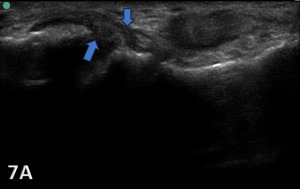

PARTIAL TEAR OF CFL

Figure 7A: The CFL will be hypoechoic and thickened or swollen in case of a partial tear and sprain (blue arrows). Partial tears might show anechoic defects and undulated or irregular ligament fibers.